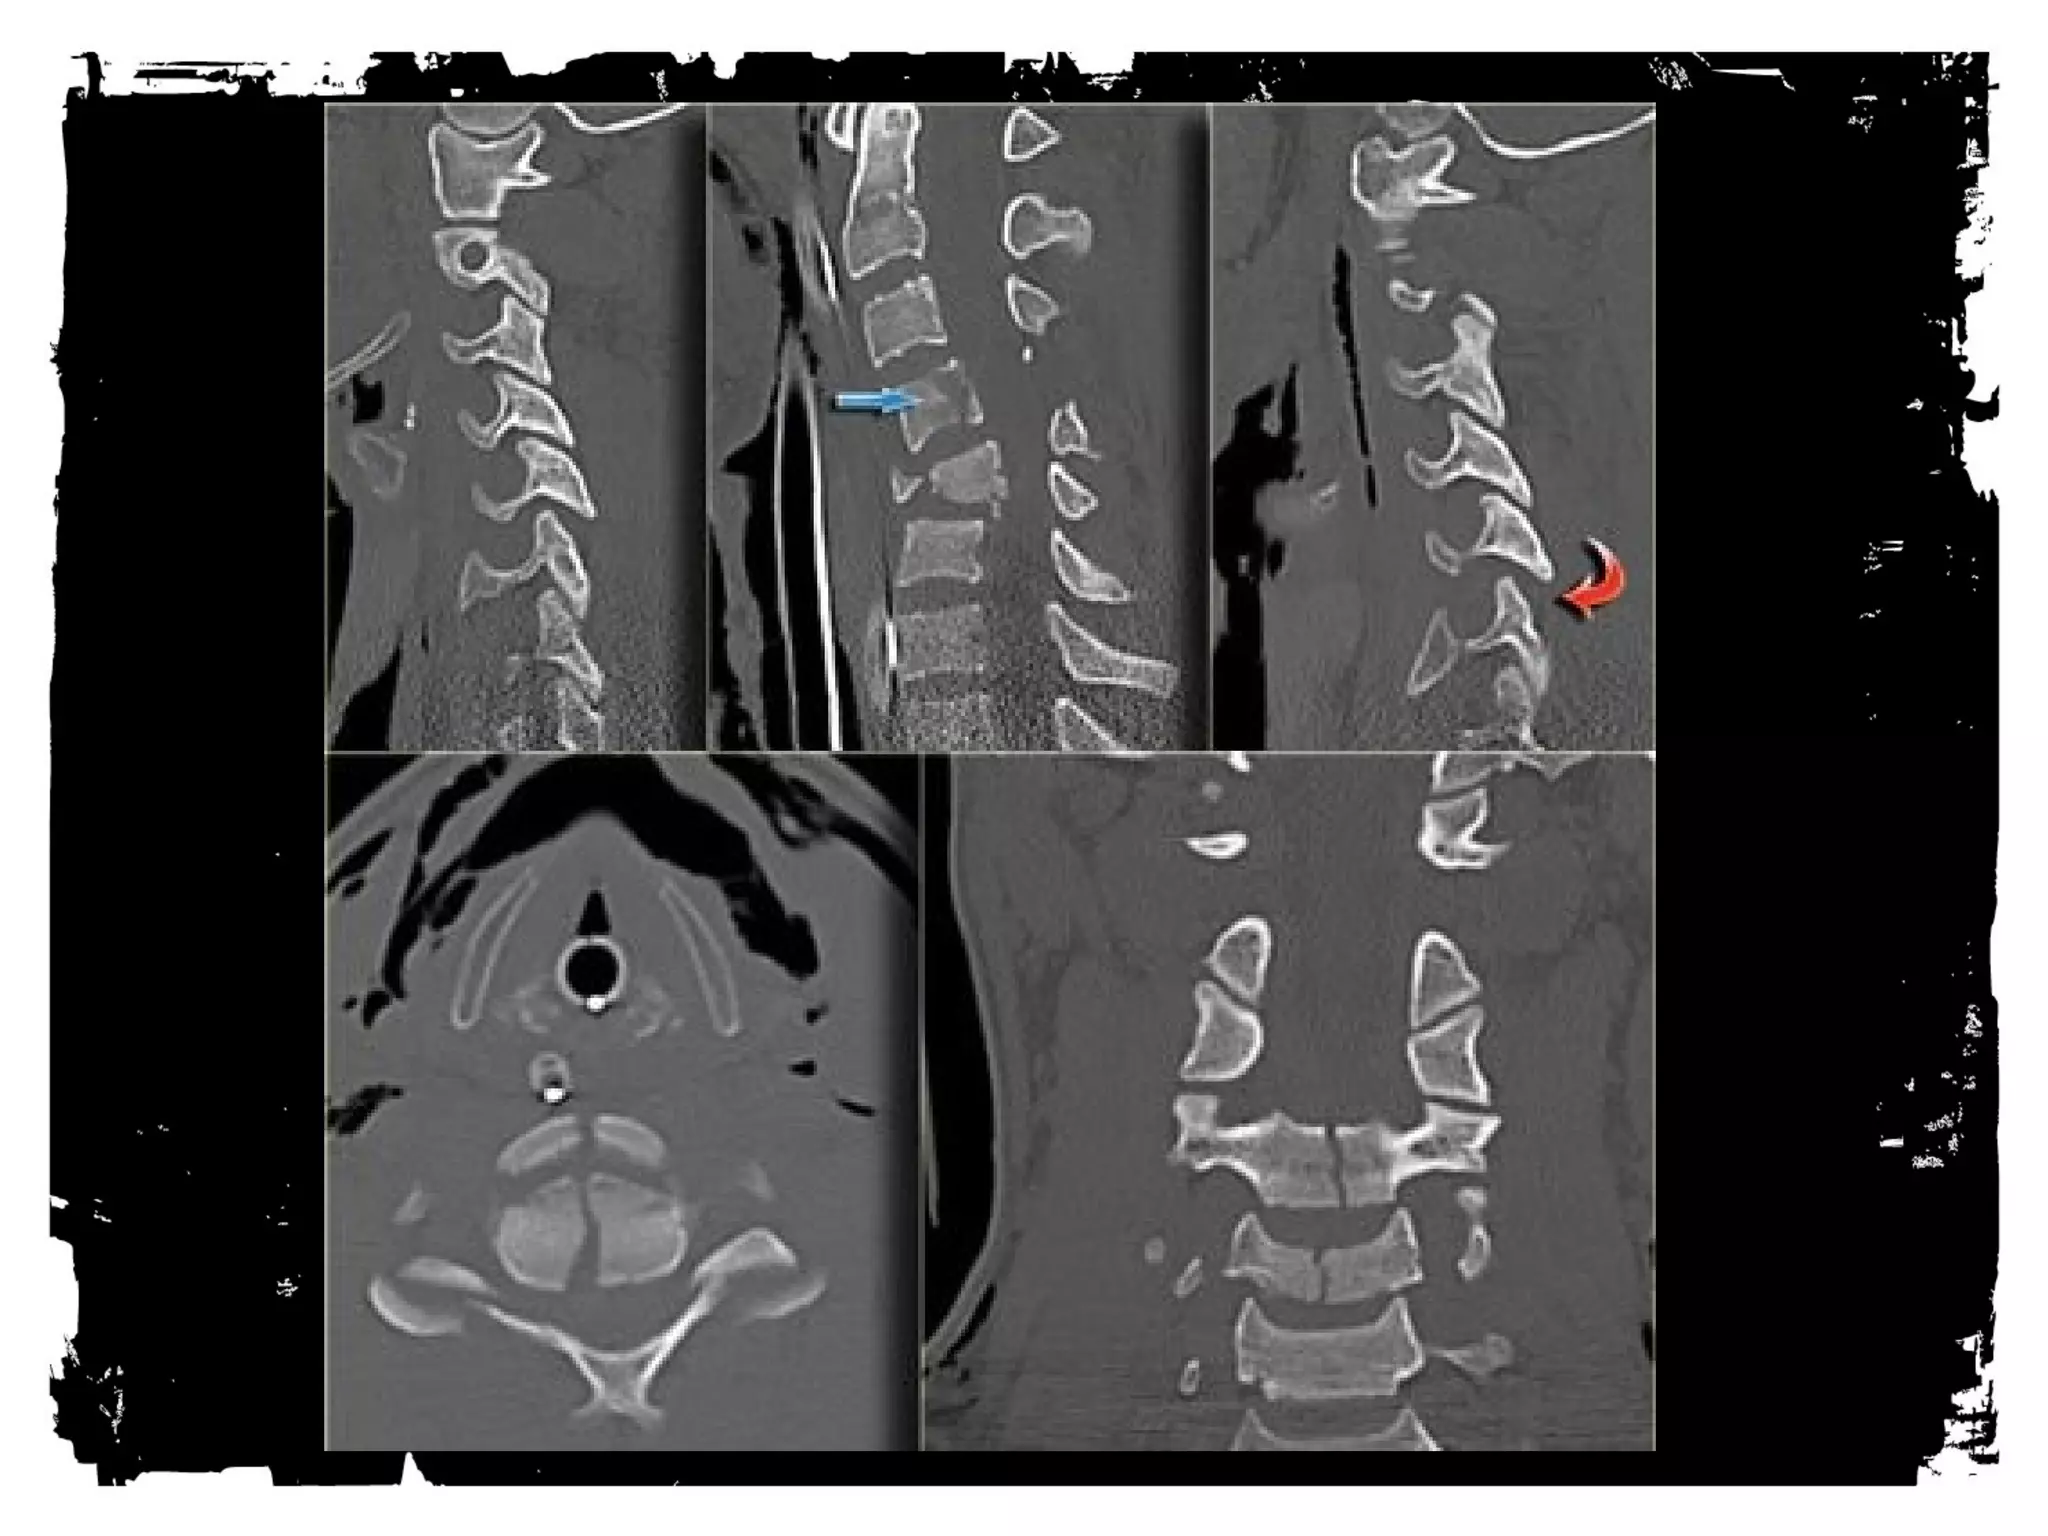

Case 1

CLICK HERE TO ADD TEXT

• Unilateral Facet Dislocation

Hyperflexion + rotation

Superior facet slides over inferior facet and becomes

locked

Anterior subluxation of superior vertebral body –25%

AP diameter

Stable injury

30% with associated neurologic deficit

MRI: disk extrusion leading to cord compression

Case (2)

Bilateral Facet Dislocation

Extreme hyperflexion

Anterior dislocation of articular masses (disruption of

posterior ligament complex,PLL,disk and ALL).

Complete dislocation: dislocated vertebra anteriorly

displaced ½ of AP diameter of vertebral body

Unstable ( high incidence of cord damage)

Case (3)

Case (4)

Flexion Tear Drop

Flexion+compression (MVA)

Teardrop fragment comes from the anteroinferior

aspect of the vertebral body

Larger posterior part displaced backward into the

spinal canal

Facets joints and interspinous distances usually

widened, disk space may be narrowed

70% of patients with neurologic injuries

Unstable fracture (complete disruption of ligaments

and anterior cord syndrome

Case (5)

Hangman’s fracture

Most common cervical spine fracture

Usually hyperextension

Unstable, however seldom associated with cord

injury (AP diameter of spinal canal greatest at C1/C2

level and # pedicles allow decompression)

Hangman’s + uni/bilateral facet dislocation: high rate

of neurologic complications

Case (6)

Hyperextension injury

Widening of disk space anteriorly and narrowing

posteriorly

“open book”

Central cord injury= disproportionated weakness in

arms and normal strength in the legs

Injuries can be devastating, however are uncommon

hemorrhagic

Case (7)

Extension Teardrop Fracture

ALL pulls bony fragment away from inferior aspect

of the vertebra because sudden extension

Fragment is true avulsion x fragment from flexion

teardrop (compression)

Lower cervical spine

Central cord syndrome (buckling of ligamenta flava

into spinal canal)

Stable in flexion; highly unstable in extension

Case (8)

Jefferson Fracture

Burst fracture of ring of C1

Axial loading in the occiput

No associated neuro deficts ( C1 ring is wide!)

> 2mm dislocation of lateral masses of C1 or

odontoid view is diagnostic, 1-2 mm is equivocal

( rotation of head?)

Predental space > 3 mm: disruption of transverse

ligament

1/3 associated with C2 fracture